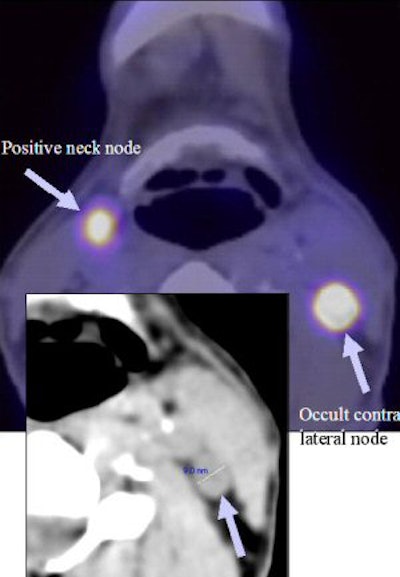

| FDG-PET/CT clinical images show a tonsillar cancer (above), a positive neck node, and lateral node (below). Images courtesy of Paul Strickland Scanner Centre. |

FDG-PET/CT also was able to detect unexpected sites of disease in six patients, who had uptake in contralateral neck nodes. In one patient, the discovery was confirmed by neck dissection, and by disease progression in another.

In four patients, the researchers were unable to confirm the FDG-PET/CT findings. "Two patients were treated with surgery to the primary site and radical neck dissection on the side of the primary site followed by chemoradiotherapy," Wong said. "One had a radical neck dissection on the side of clinical disease followed by chemoradiotherapy, and one other patient had palliative radiotherapy."